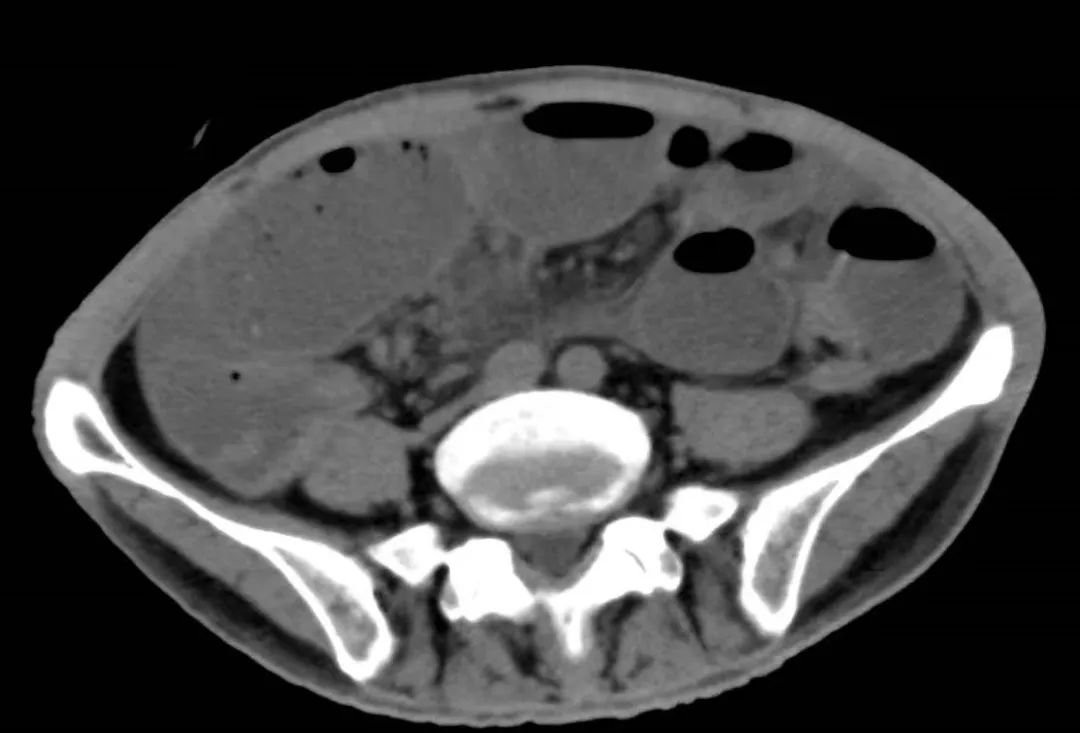

2022年5月的一个凌晨,一位93岁的老奶奶因为腹胀和呕吐被送到了新龙泽院区急诊科,经过问诊和初步查体后,接诊医生考虑患者存在肠梗阻,立即为患者申请了急诊腹部CT检查,结果显示患者的升结肠存在一个巨大的肿物堵塞了肠腔。在给予补液和胃肠减压的同时,普外科立即对患者的病情进行了紧急评估和讨论。肿瘤导致患者出现肠梗阻,手术是唯一的解决方案,但患者高龄且身体非常瘦弱,围手术期发生肺部感染、心脑血管事件等并发症的概率非常高。普外科高鹏骥主任医师制定了急诊实施腹腔镜下右半结肠切除的手术方案,并在麻醉科和手术室医护团队的密切配合下顺利完成了手术。